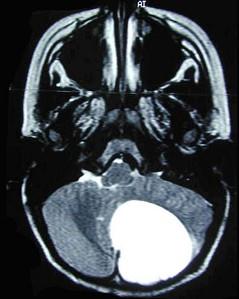

问题 星形细胞瘤(如图所示)的特点()

选项 A.最常见的颅内胶质瘤 B.多见于大脑半球,界限清楚 C.中青年多见 D.儿童以小脑半球多发 E.实质性肿瘤手术切除可以根治

答案 ACD